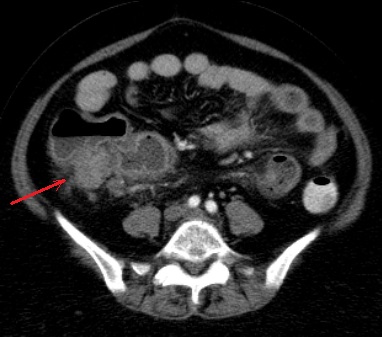

Image radiologique TDM et image de PET/CT des

adenocarcinomae du colon en extension localise et extension

metastasique :